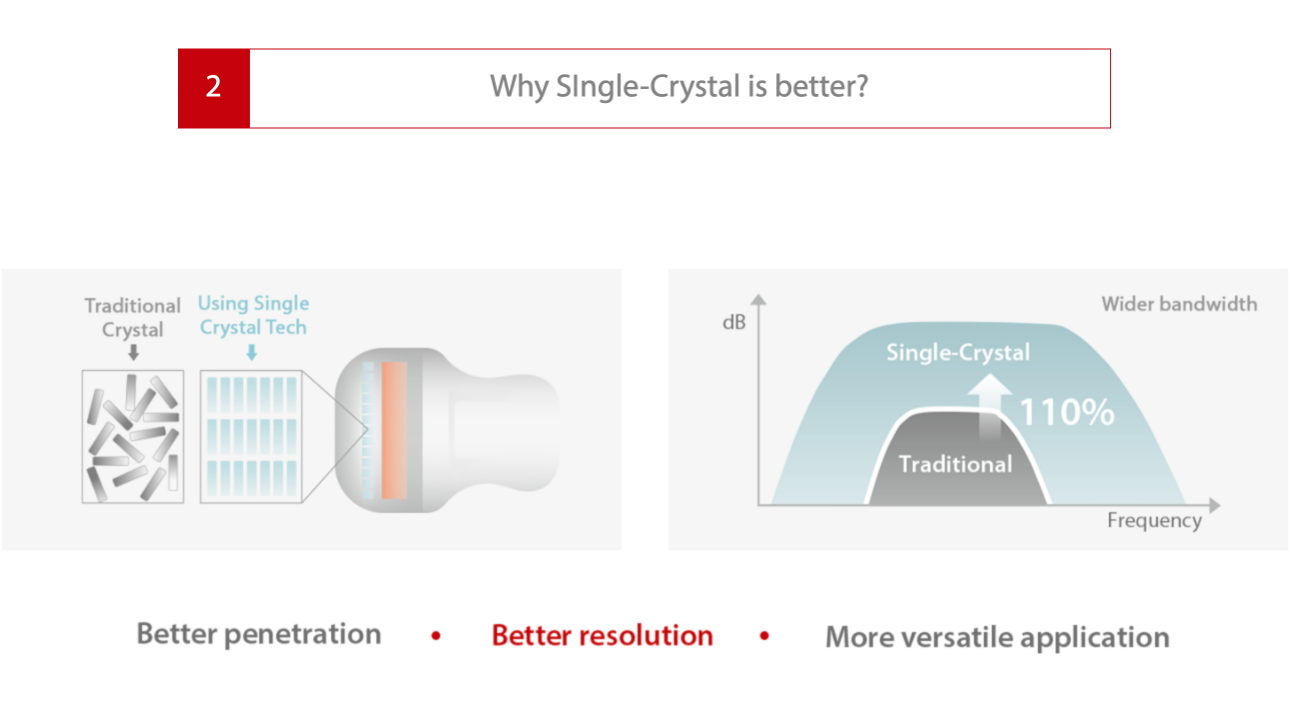

Tek Kristal Katman

Tek Kristal Katman